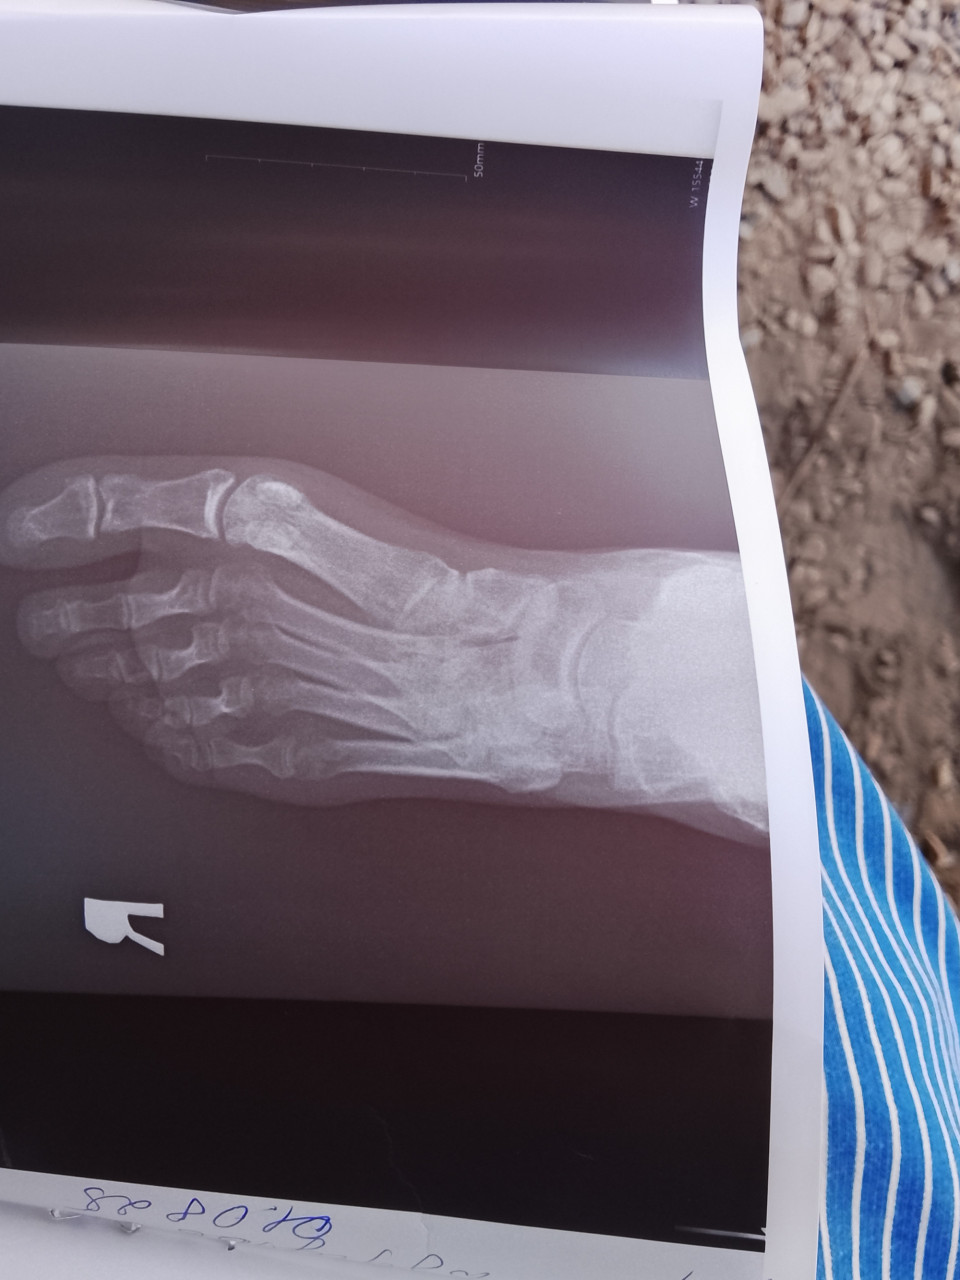

4месяца назад был перелом таранной со смещением сейчас говорят артроз запущенный подскажите пожалуйста чего именно

Здравствуйте. По рентгену видно, что суставная щель в области таранно-пяточного и таранно-ладьевидного суставов сужена, контуры костей неровные  это признаки посттравматического артроза, вероятно из-за нарушенного восстановления после перелома таранной кости.

Здравствуйте. Речь о подтаранном и таранно-ладьевидном артрозе. Это осложнение типично после переломов таранной кости со смещением. Рекомендуется консультация ортопеда для обсуждения вариантов лечения  от физиотерапии и ортезирования до оперативного вмешательства при выраженной боли.